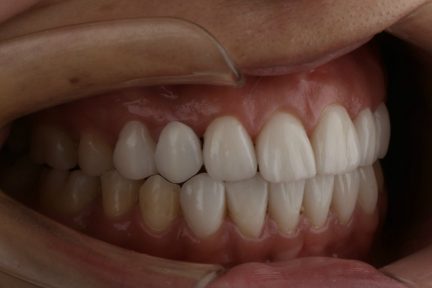

Classe I, morsure bord à bord, espacement, diastème

Facettes

Avec l'aimable autorisation du Dr F. Wang, 2021

Synthèse du traitement

Résultats obtenus

- Relation de Classe I obtenue

- Guidage fonctionnel des canines des deux côtés

- Surplomb et recouvrement normaux obtenus

- Ligne esthétique du sourire obtenue

- Cas où tous les objectifs de traitement ont été atteints

- Arcades harmonieuses obtenues

Commentaires

- Il s'agit d'un cas d'orthodontie combinée à une réparation esthétique.

- Il était nécessaire d'améliorer l'occlusion et la répartition de l'espace grâce à Invisalign et d'améliorer la forme et la beauté des dents du patient grâce à une restauration esthétique.

- Avant le traitement orthodontique, le patient a utilisé la conception esthétique DSD pour répartir l'espace, et l'espace dispersé en dehors de la zone esthétique a été ajusté par le mouvement proximal de la dent postérieure.

- Après traitement orthodontique, la partie supérieure droite 3, un implant posé et toutes les dents antérieures ayant reçu une restauration esthétique ont été utilisées.

- Le patient était très satisfait de l'effet curatif.

- Il est à noter que ce cas a été réalisé en une seule fois, aucune finition ne fut nécessaire.

État initial

État final